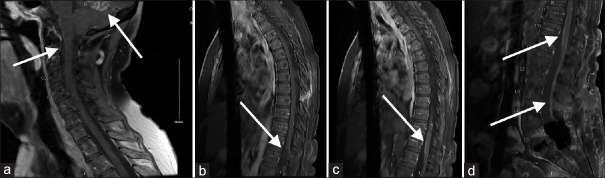

Sugar-Coating or Zuckerguss Appearance on Magnetic Resonance Imaging in Leptomeningeal Carcinomatosis in a Patient with Acute Myeloid Leukemia.